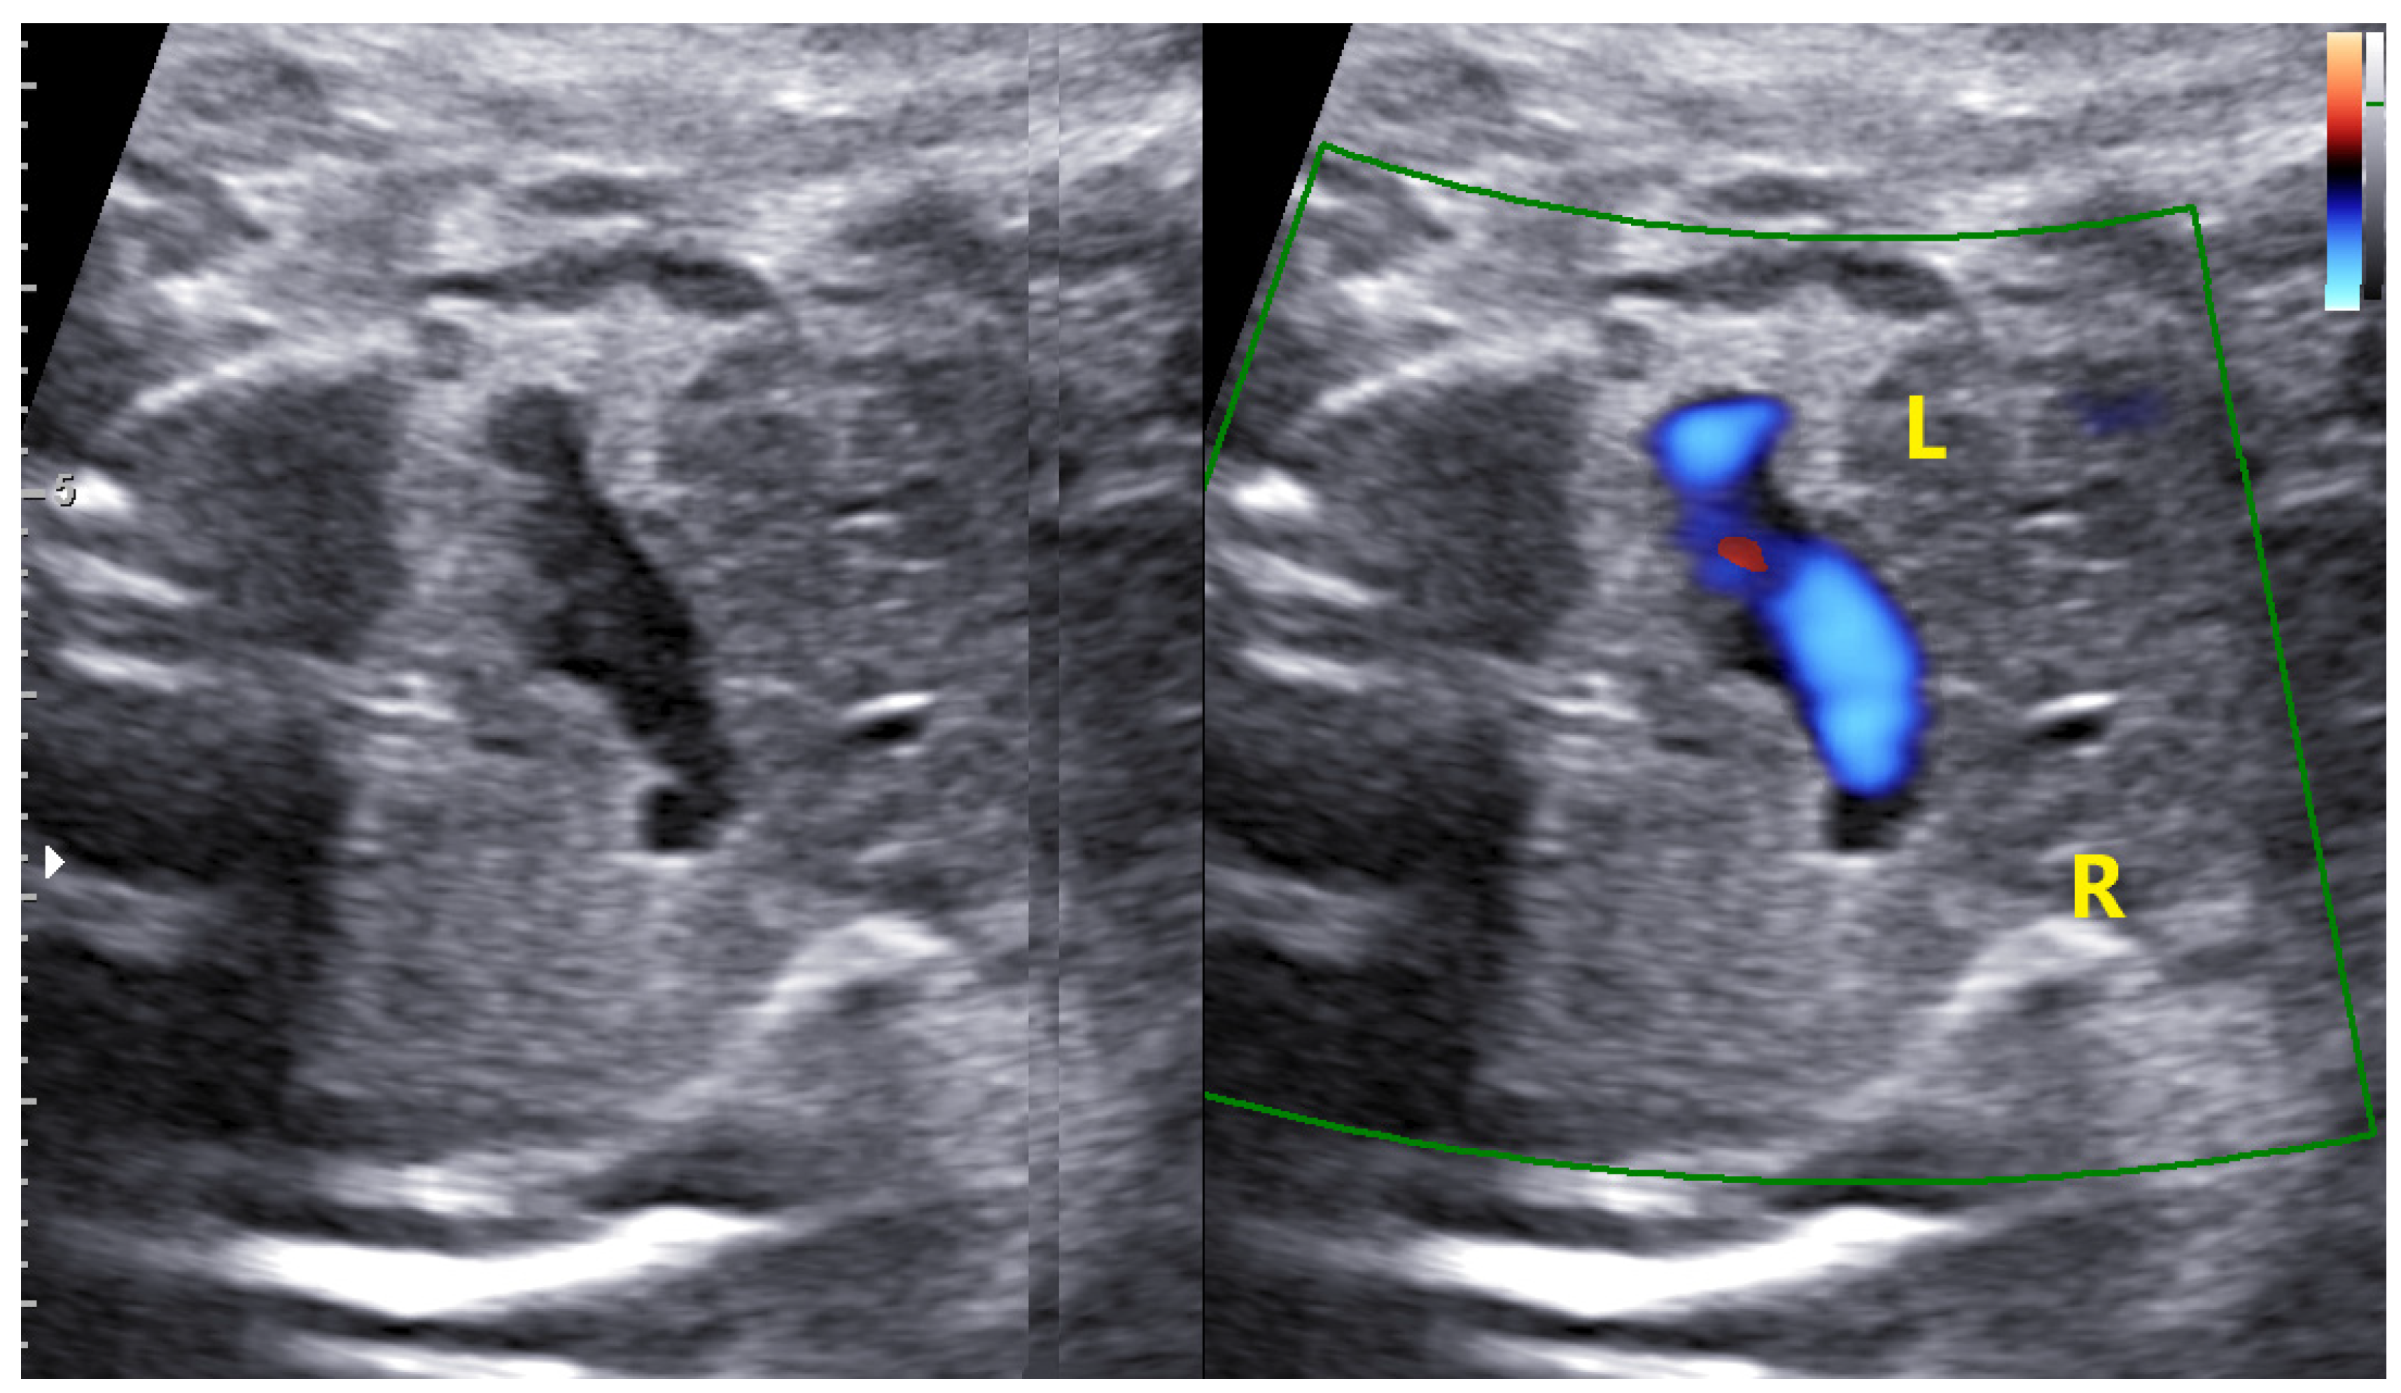

4. Cases—Ultrasound Findings Description

4.1. Case 1

4.2. Case 2

4.3. Case 3

4.4. Case 4